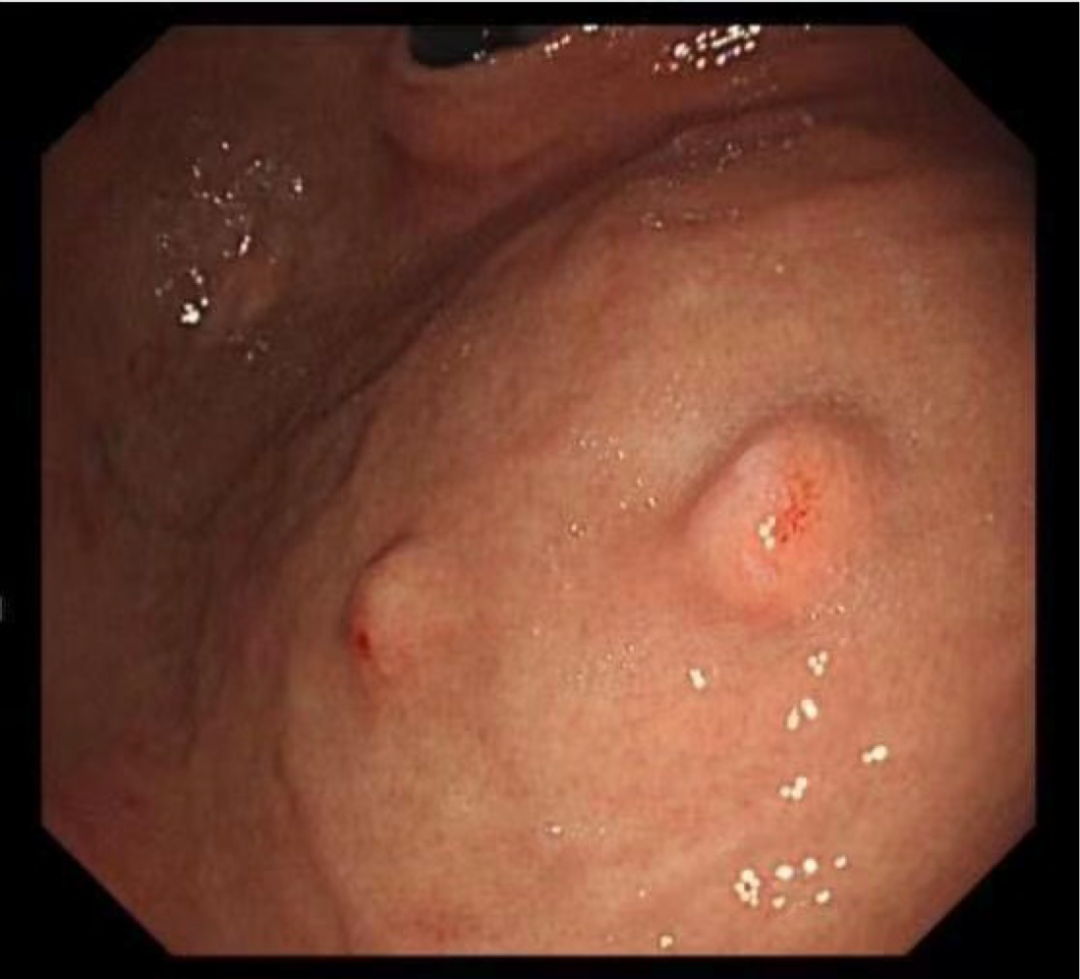

病例一:

孙某某,女,65岁,因间断上腹痛10余天完善胃镜检查,胃体上段见两处直径0.5-0.8cm黏膜下隆起,超声内镜见病变起源于固有肌层,呈低回声改变,截面大小5.5*6.0mm。

考虑间质瘤,因有增大并恶变的风险,与患者家属详细沟通、解释病情,完成充分的术前评估及准备后,孙院长实施内镜下胃全层切除术,成功将病灶切除;术后病理诊断示“胃间质瘤,患者康复出院”。